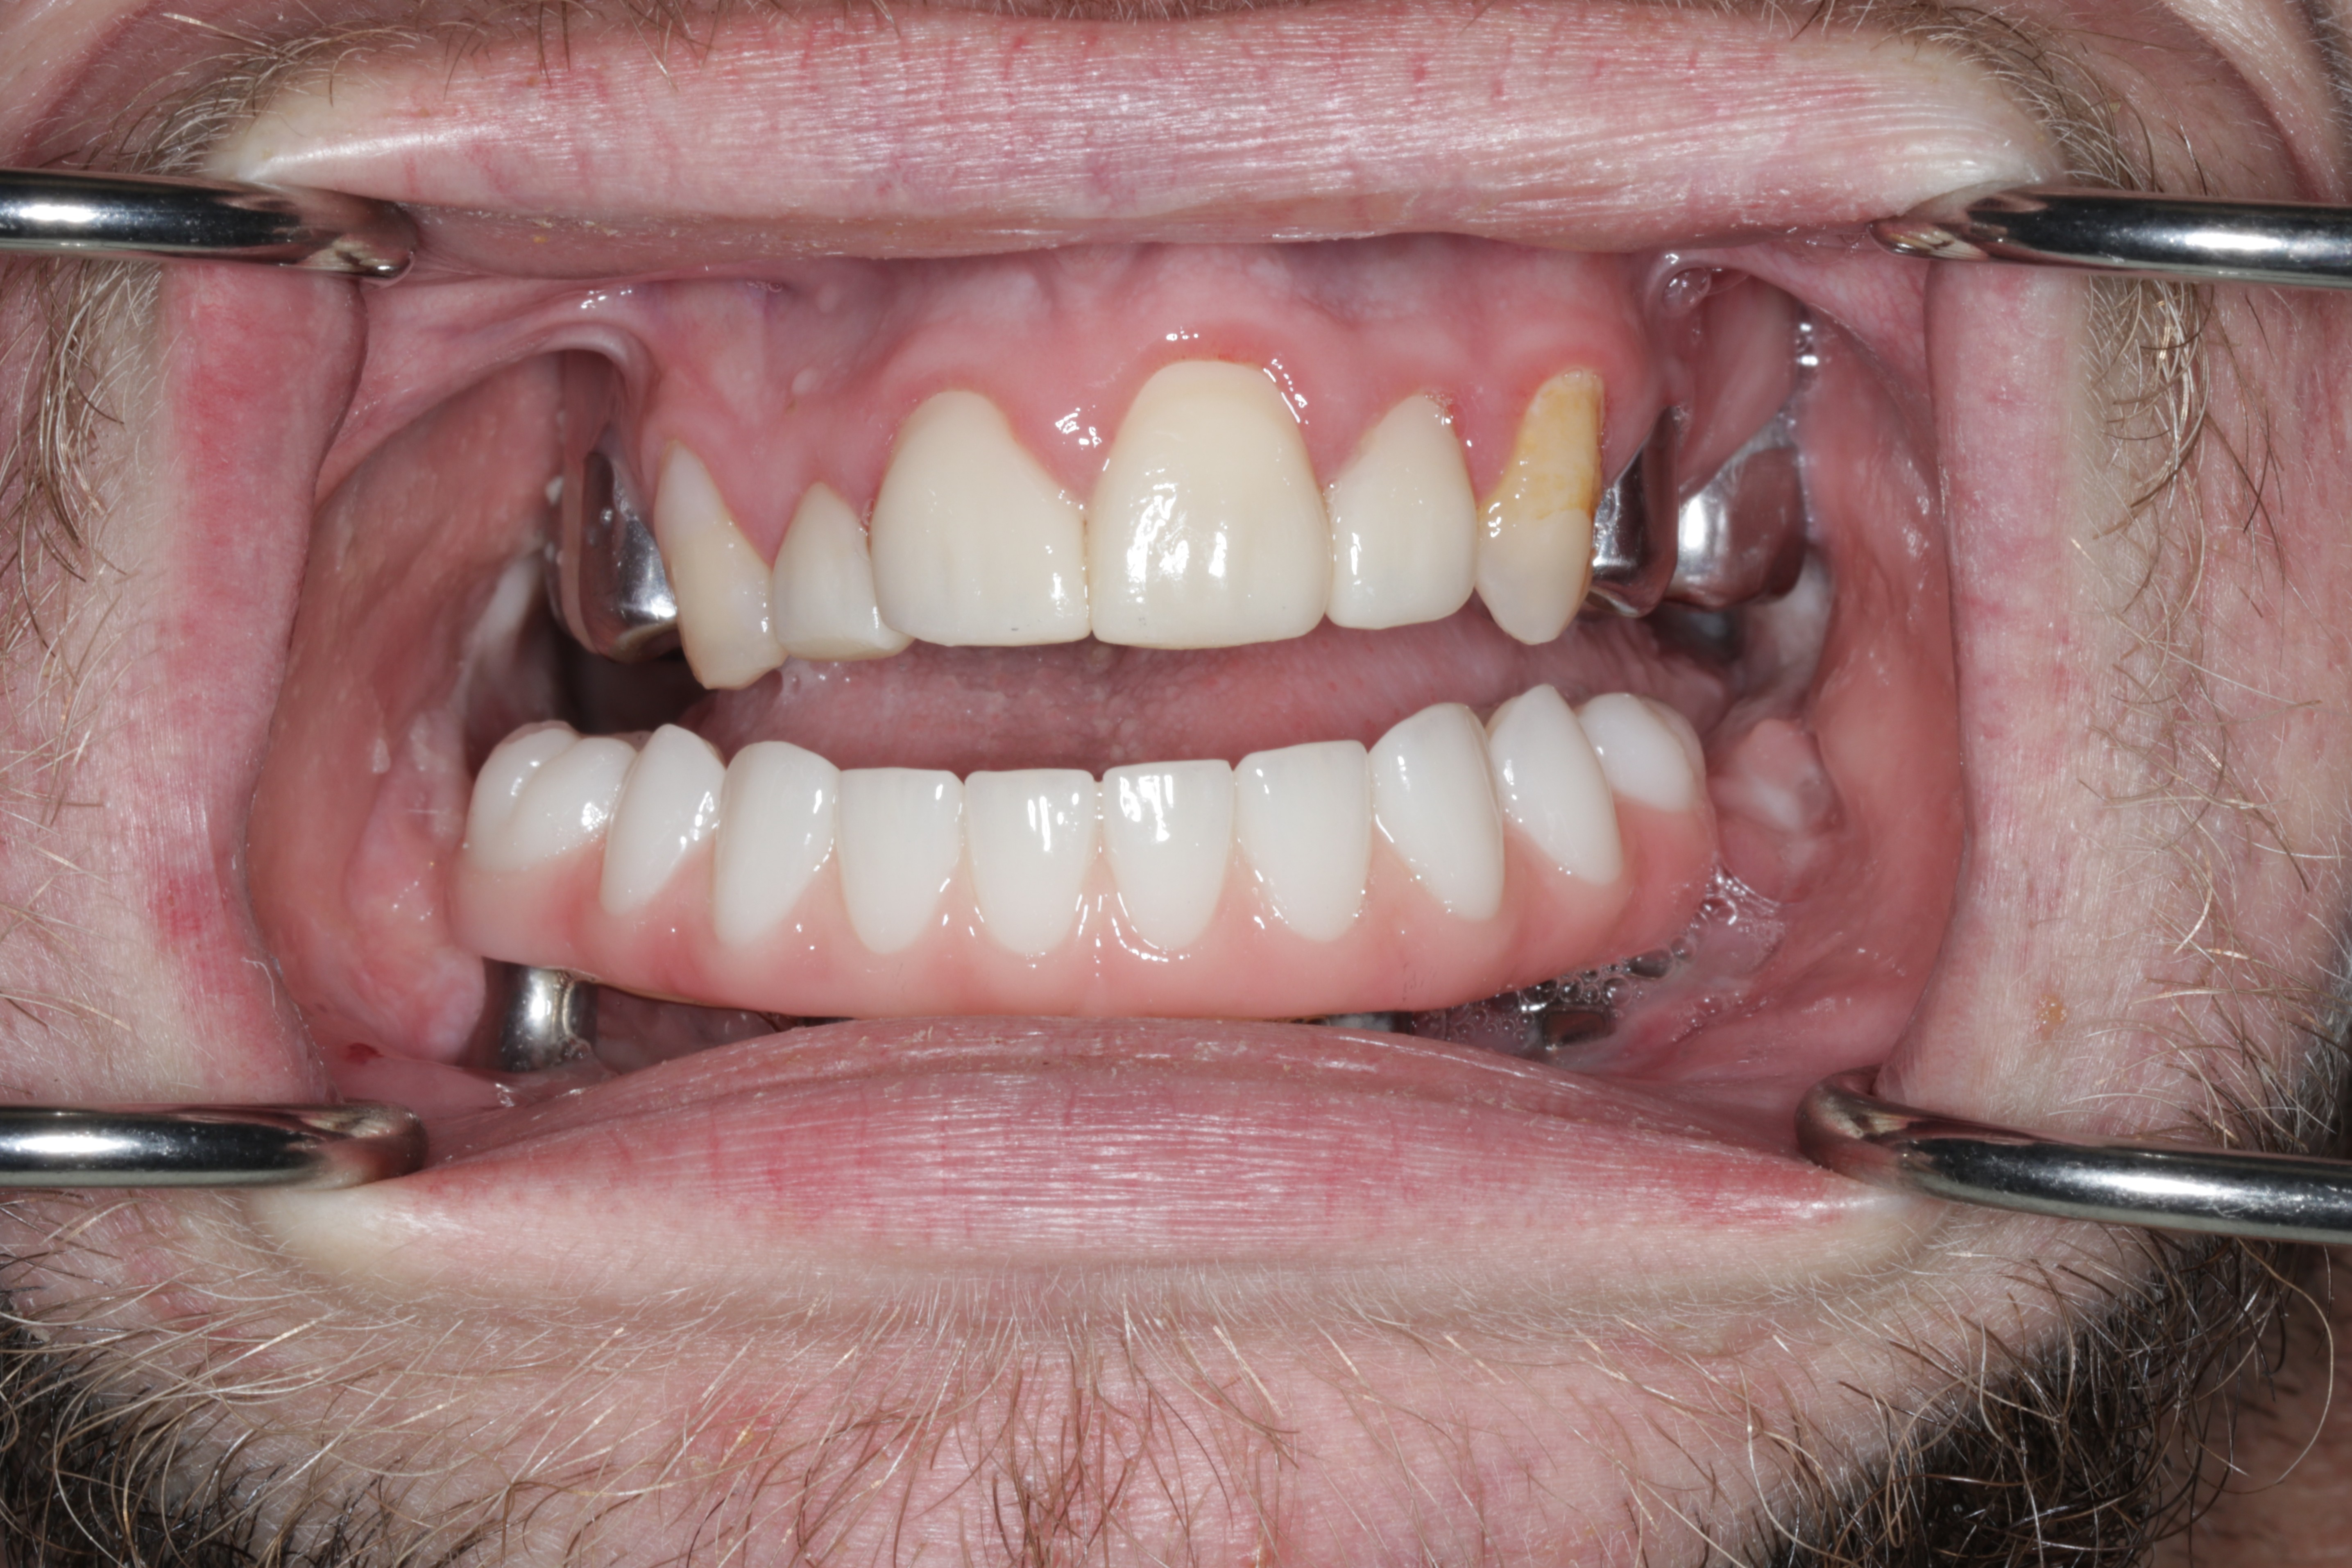

A 21-year-old male with CCMS presented with complete mandibular edentulism, severe mandibular atrophy, and limited oral opening. Retained maxillary dentition was present.

Records for this patient were collected using a dual-scan CBCT and intraoral scanning. A surgical planning session was completed with KLS Martin for the fabrication of a CAD-CAM subperiosteal implant system with immediate loading of a mandibular prototype (Figs 2-5).

A custom occlusal splint confirmed mount and prosthetic space. The site was closed with resorbable sutures intraorally and plain gut at trocar sites. Recovery was uneventful, and the patient progressed to prosthetic rehabilitation (Figs 9 and 10).

Maxillary scanning was performed after prototype removal. Bite registration scans were captured after reseating the prototype and verifying occlusion. An updated prototype was fabricated, adjusted minimally, and worn for four weeks before fabrication of final prothesis.

The refined prototype was rescanned on the back-pour cast, and a definitive monolithic implant supported fixed zirconia prosthesis was fabricated and successfully delivered (Figs 16 and 17).